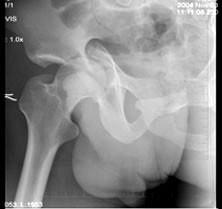

问题 32岁男性患者,因车祸致右髋关节肿痛,活动受限摄片如图示,最佳诊断是 ( )

选项 A、骨盆Ⅳ型骨折 B、以上都不是 C、骨盆Ⅱ型骨折 D、骨盆Ⅲ型骨折 E、骨盆Ⅰ型骨折

答案 A